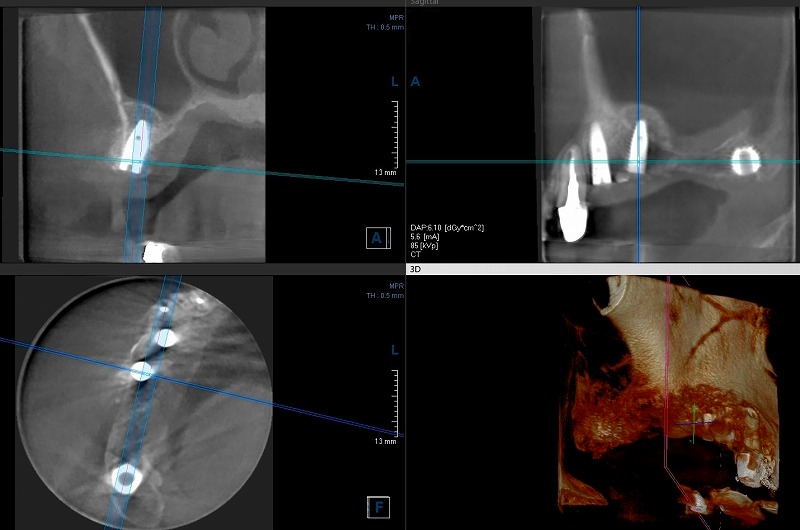

上の奥歯が四本無くて、そこに三本のインプラントを埋めました。下のレントゲン写真はCTの写真です。左下が水平の断面で上の二つが前からと横からの垂直断面です。

一番前(写真では右上側の写真の一番左側のネジ)のインプラントは高さが十分で、普通のサイズのインプラントが入りました。

前から二番目は、骨の高さが不足していたので、ソケットリフトという方法で、鼻の空洞に骨を作る素材を入れました。

上の四枚の写真の右上の所で、青い縦の線が入っている所にあるインプラントは、上側の先の方三分の一が鼻の空洞に飛び出しているのでその先端あたりにドーム状のふくらみができています。

これは、ドリルで掘ったインプラントのための穴から骨を作る素材を入れたためにできた人工のドームです。

一番奥(写真では右側)のインプラントは、骨の高さが全く不足していてショートインプラントが入っています。ここも、ソケットリフトで骨を上に作りたかったのですが、鼻の粘膜がやや厚くなっていてもしかすると炎症を起こして敗れる可能性が有ったのでソケットリフトはしませんでした。かなり奥の方の歯なのでかなりしにくいという理由も有ります。